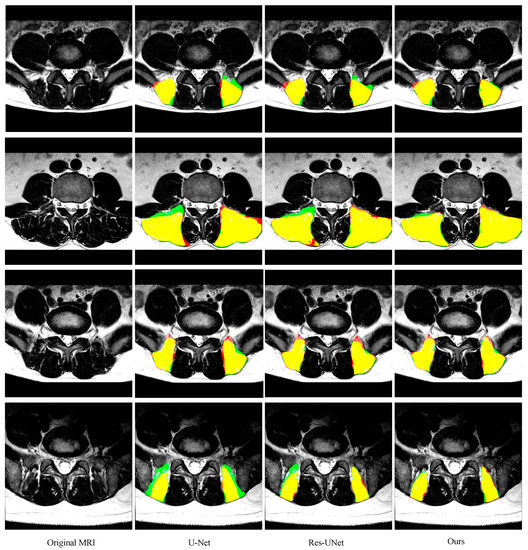

3.5. Comparison with other State-of-the-Art Methods